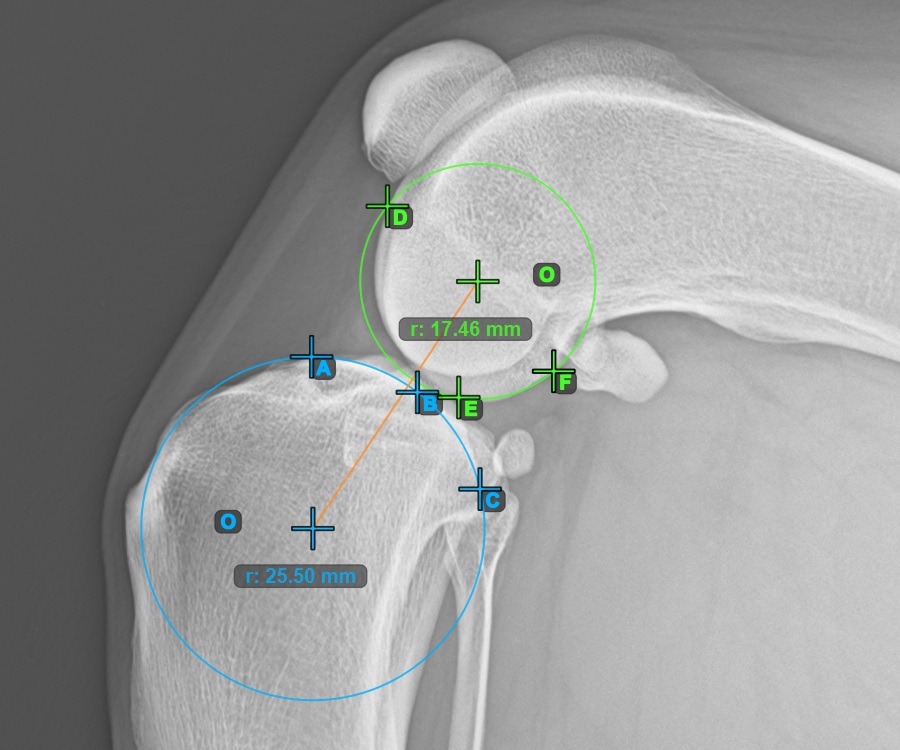

Mark one point in front of the joint on the common tangent between the two main condylus circles. A line will be drawn automatically through the marked point.

The image below represents a typical placement of the point on the common tangent between the two circles.